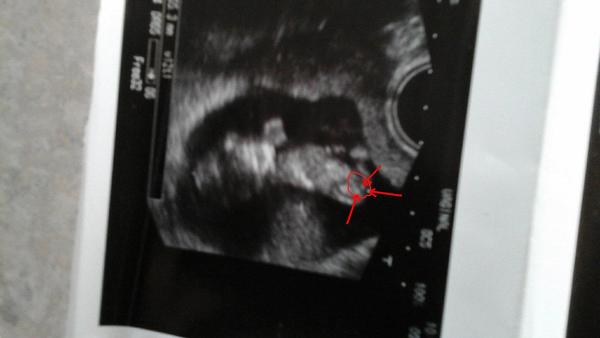

ja bych tipla, ze dole je hlava a ruce ma za hlavou takže to nahore v pravo je noha a druhe neni videt a to mezi je bimbas 😀

To je teda děsná fotka🙂 Ale mi se zas zdá, že hlava je nahoře, mimi jakoby sedí a dole vidím spíše ,,kávové zrno''... Tak a teď si vyber😀

podle mě to nejsou varlátka ale kávové zrníčko, tak myslím že to bude holčička 🙂

V 17 tt. je to zatím hodně nejisté, počkala bych do 20 tt. na velký UTZ